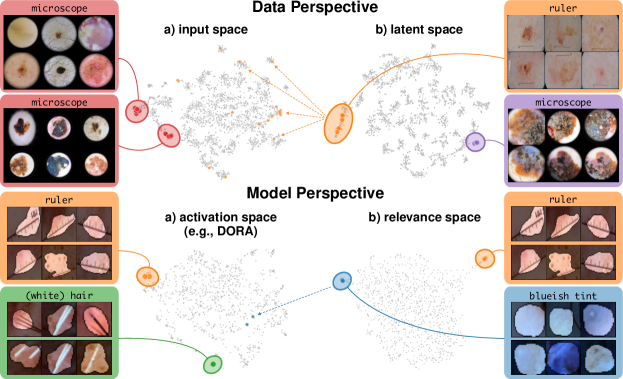

4.1 Data Perspective – Detecting Spurious Samples

A first line of works assumes that models use a different behavior for spurious samples compared to “clean” samples. Concretely, model behavior can be estimated using local attribution methods, such as Input Gradients [51, 65], GradCAM [64], or LRP [4]. Note, that backpropagation-based attribution approaches distribute relevance scores from the output through all layers to the input, enabling the analysis of both input heatmaps and latent relevance scores. This allows the analysis of prediction behavior at different abstraction levels, represented as relevance scores for samples in layer with channels and spatial dimension , or (spatially) aggregated representations. Using a distance function, such as cosine distance, we compute a pairwise distance matrix for further inspection.

Both input and latent relevance clustering require subsequent human supervision to determine whether outlier clusters represent valid or spurious behavior. To semi-automate this process, Anders et al. [3] propose using Fisher Discriminant Analysis [37] to rank class-wise clusterings by linear separability, while Dreyer et al. [27] computes similarities between prototypes. The results of clustering approaches can serve as an initial set for bias modeling methods outlined in Sec. 3.2, which can be refined iteratively. An example outlier cluster of latent relevances is shown in Fig. 4 (top), with all samples containing the spurious band-aid concept.

4.2 Model Perspective – Detecting Spurious Representations

In contrast to detecting spurious samples, recent work focuses on identifying spurious model internals directly. This aligns with mechanistic interpretability, which seeks to decipher the internal mechanics of DNNs [56, 31, 13]. As outlined in Sec. 3.1, various global XAIs methods aim to explain the role of individual neurons, and these insights can be leveraged to detect spurious model internals by clustering learned concepts and identifying outliers. Given input data with samples, Pahde et al. [59] compute spatially aggregated relevances . Subsequently, they compute the pairwise cosine distance per column (i.e., channel/concept) and embed the resulting distance matrix in a low-dimensional space using dimension reduction techniques like t-Distributed Stochastic Neighbor Embedding (t-SNE) [71] or Uniform Manifold Approximation and Projection (UMAP) [49]. This low-dimensional embedding can be visualized to identify outliers through human inspection or anomaly detection algorithms, such as the Local Outlier Factor [12]. In summary, outlier representations can be identified in an embedding representation , obtained as

where reduces the dimension to , and the pairwise distance function is applied along all channel dimensions in the latent representation , either given by activations or relevance scores for layer . Note that this approach assumes over-parameterization resulting in redundant neurons, allowing to distinguish between similar and dissimilar concept representations. An example is shown in Fig. 4 (bottom), where latent relevance scores from a ResNet50 model trained for melanoma detection are used to identify outlier concepts, specifically a cluster focusing on band-aids rather than clinically relevant features. Notably, Eq. 3 can easily be extended to find outlier directions instead of neurons. Specifically, this involves a linear transformation of latent representations using the directions of interest, e.g., obtained in unsupervised manner as described in Sec. 3.1.

Similarly, DORA embeds a pairwise distance matrix of neuron representations into 2D, but proposes a data-agnostic approach and a tailored distance function [16]. Specifically, they generate ActMax samples as concept representation for neurons, referred to as natural Activation-Maximization signals (n-AMS). Each neuron is represented by a representation activation vector , measuring how much other neurons activate on the given n-AMS, and compute pairwise distances between the vectors. The resulting distance matrix is embedded into lower dimension to identify outlier representations. Notably, instead of generating ActMax samples, this approach can also be applied on real samples from a reference dataset.

Data Perspective

We first apply SpRAy in input and latent space, computing input feature importance scores using LRP summed over color channels. To obtain latent relevances, we use intermediate relevance scores in the LRP computation process after the (out of four) residual block, max-pooling over spatial dimensions to yield relevance scores for layer with channels. The clustering of pairwise cosine distances between heatmaps is shown in Fig. 6 (top left). Detected outlier clusters contain samples with spatially coherent biases, e.g., the black circle around the lesions originating from microscopes (). In contrast, clustering latent relevance scores reveals more complex, less spatially dependent clusters, as shown in Fig. 6 (top right), including the ruler artifact () and the microscope (). Compared to those in input space, the cluster for the microscope in latent space represents a more diverse high-level concept. In the input space visualization, we further highlight samples from the ruler cluster detected in latent space. Instead of forming a cluster, they spread across the entire embedding space, indicating that the bias is too complex to be detected in input space.

Model Perspective

Next, we apply bias identification approaches from the model perspective by identifying outlier neurons based on activation pattern via DORA and relevance pattern by clustering pair-wise cosine distances between concept relevance scores. We focus on latent activations and relevances after the third residual block. DORA uses a distance function based on how neurons activate upon each others n-AMS, achieving high similarity when neurons activate upon similar input signal. A 2D visualization of the resulting distance matrix is shown in Fig. 6 (bottom left). Identified outlier concepts include ruler () and (white) hair (). We further compute pairwise cosine distances between latent relevance scores , aggregated over spatial dimensions, and apply UMAP to embed the resulting distance matrix in . This results in high similarity between neurons (concepts) that the model uses similarly for predictions. The concept clustering is visualized in Fig. 6 (bottom right), highlighting two outlier clusters focused on rulers () and blueish tint ().